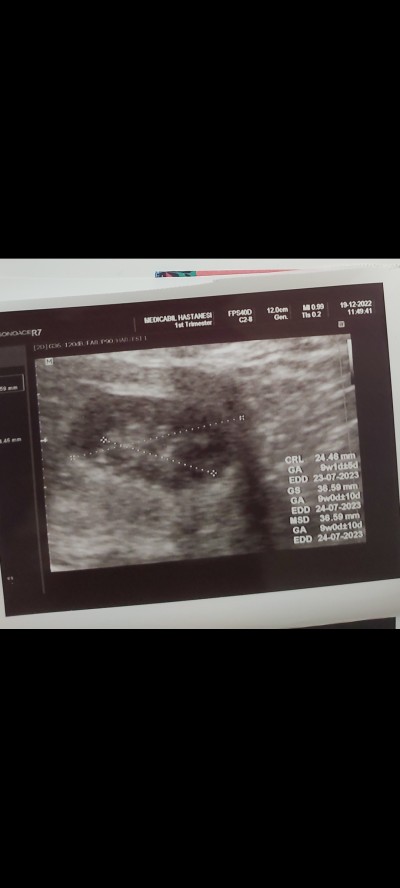

Kızlar çok kafama takılıyor ultrason görüntüm hep çok silik gibi sanki diğer herkesin ultrason görüntüsüne bakıyorum kese bebek çok belirgin oluyor benimki asla öyle değil 72 kiloyum ondan mı böyle bilmiyorum bu konu hakkında bilgisi olan var mı 9 haftqlık hamileyim

Gebelik haftası 9+1